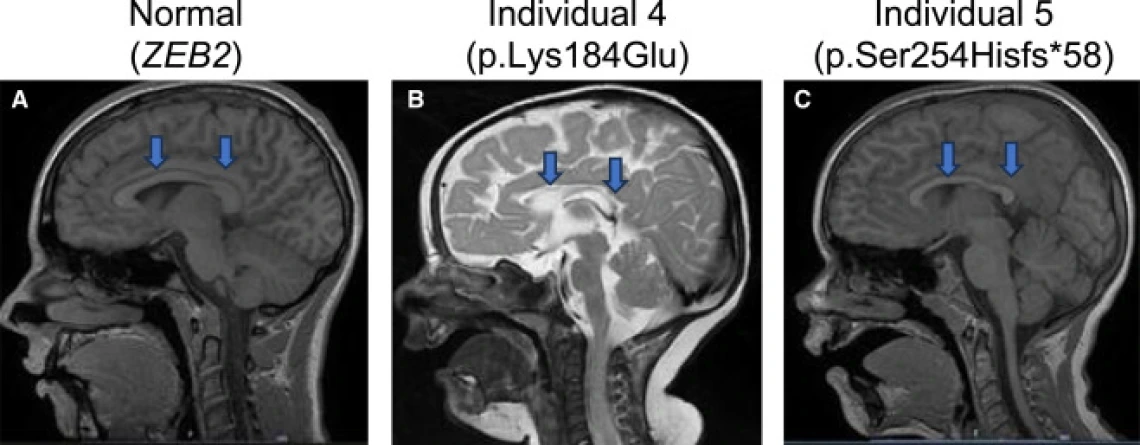

MRI Scans of 3 Individuals Displaying Variances in Regions of the Brain

Dr. Martha Bhattacharya, together with researchers in her lab and collaborators worldwide, uncovered that mutations in TMEM184B cause a newly recognized neurodevelopmental disorder marked by seizures and altered brain structure. Their work connects this conserved gene to key metabolic pathways that shape early brain development.